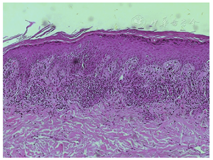

皮肤科检查:颈部、左侧乳房下皱褶、左侧腘窝、左侧腹股沟可见沿皱褶方向分布的紫红色斑丘疹,其中颈部、左侧乳房下皱褶、左侧腘窝皮损可见白色网状条纹,无脱屑(图1)。全身其他部位皮肤及口腔、生殖器黏膜无类似皮疹。皮肤镜检查:颈部、左侧乳房下皱褶皮损可见白色网状条纹伴周围放射状分布的线状血管及色素沉着;左侧腘窝皮损可见模糊的白色网状条纹伴周围少量放射状分布的线状血管、线状不规则血管及蓝灰色点、球;左侧腹股沟皮损可见大片瘢痕样色素减退区伴周围少量不规则血管及色素沉着(图1)。左腹股沟区皮损组织病理:表皮角化过度,角化不全,棘层锯齿状增厚,基底细胞液化变性,真皮浅层淋巴细胞呈带状浸润,并见噬黑素细胞(图2)。

Wickham纹是扁平苔藓皮肤镜下的特征性表现,呈白色线状、网状、放射状、圆形、球状、垂直线状和面纱样,对应于组织病理学上的颗粒层增厚。有学者[4]发现,Wickham纹主要见于活动期皮损,治疗后消失,是疾病活动的标志。本例患者颈部皮疹肉眼呈红色丘疹,可见线状Wickham纹;皮肤镜下见清晰的线状、放射状白色条纹,周围可见放射状分布的线状血管、色素沉着,符合典型活动期扁平苔藓皮肤镜下表现。左侧乳房下皮疹与颈部类似,肉眼及皮肤镜下Wickham纹稍模糊。腘窝处皮疹肉眼见模糊的Wickham纹及少量色素沉着,此时皮肤镜下可见较模糊、边界不清的浅白色条纹,放射状分布的线状血管、线状不规则血管及少量蓝灰色点、球。腹股沟区皮疹呈淡红色斑丘疹,未见Wickham纹,皮肤镜下见大片瘢痕样色素减退区,边界模糊,周围可见少量不规则血管及色素沉着。以上4个部位皮疹对应于扁平苔藓的不同阶段,皮肤镜下表现亦有所差异,活动期可见清晰的Wickham纹,随后变得模糊、边界不清,消退期则为瘢痕样色素减退,缺乏扁平苔藓的特征性表现,呈动态变化过程。本例患者仅对左腹股沟区皮损进行组织病理检查,显微镜下颗粒层略增厚,真皮上部较多噬黑素细胞,符合皮肤镜下色素沉着及无明显Wickham纹的表现。